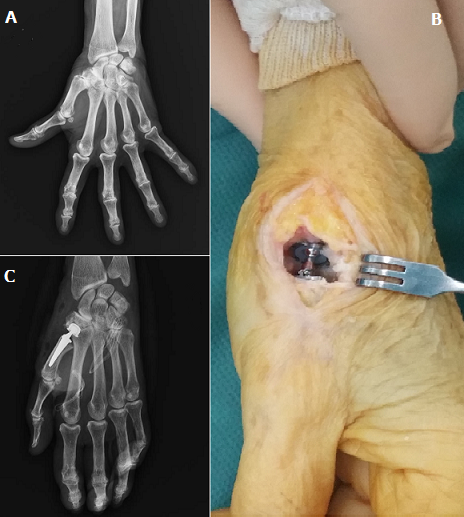

Il s’agit d’une patiente âgée de 70 ans qui présente depuis 3 ans des douleurs évoluant par crises situées à la racine du pouce avec enraidissement progressif du pouce. Chez qui l’examen clinique trouve une déformation du pouce en Z, avec diminution de force de la pince pouce-index. Le bilan radiologique de la colonne du pouce a mis en évidence une arthrose trapézo-métacarpienne (A). La patiente a bénéficié au début d’un traitement médical à base d’anti-inflammatoire puis des infiltrations de corticoïdes associé à une orthèse du pouce. Devant la persistance de la douleur et diminution de la mobilité du pouce, un traitement chirurgical a été préconisé par remplacement prothétique de l’articulation trapézo-métacarpienne (B, C). L’évolutionétait favorable avec disparition de la douleur et récupération de la force et de la mobilité du pouce.